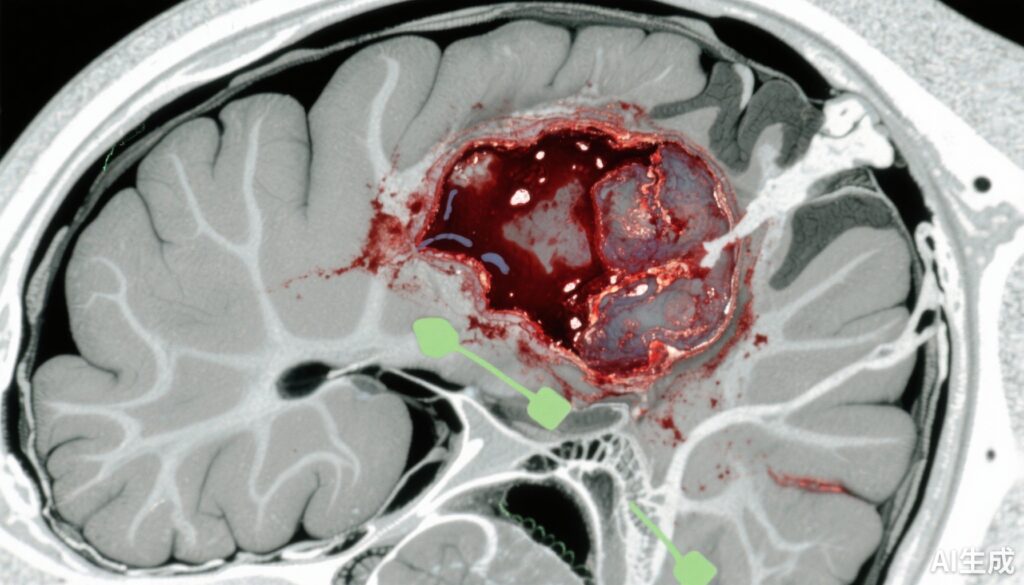

Chấn thương não (TBI) vẫn là nguyên nhân chính gây ra tật và tử vong trên toàn thế giới, với huyết chũ cấp tính (ASDH) là một trong những tổn thươngintracranial nguy hiểm nhất. ASDH xảy ra do chảy máu giữa màng cứng và bề mặt não, thường do chấn thương đầu, dẫn đến tăng áp lực nội sọ và có thể gây ra di chứng. Cách quản lý truyền thống bao gồm phẫu thuật cấp tính để giảm tác động khối u và chấn thương não thứ phát. Tuy nhiên, sự đa dạng về mức độ nghiêm trọng của chấn thương và các yếu tố bệnh nhân đã để lại sự không chắc chắn về việc liệu phẫu thuật ngay lập tức có mang lại kết quả tốt hơn so với điều trị bảo thủ trong nhiều trường hợp. Sự không chắc chắn này tạo ra sự biến đổi trong thực hành lâm sàng và nhấn mạnh nhu cầu y tế chưa được đáp ứng để làm rõ các chiến lược điều trị tối ưu, cân bằng rủi ro và lợi ích trong quản lý ASDH.